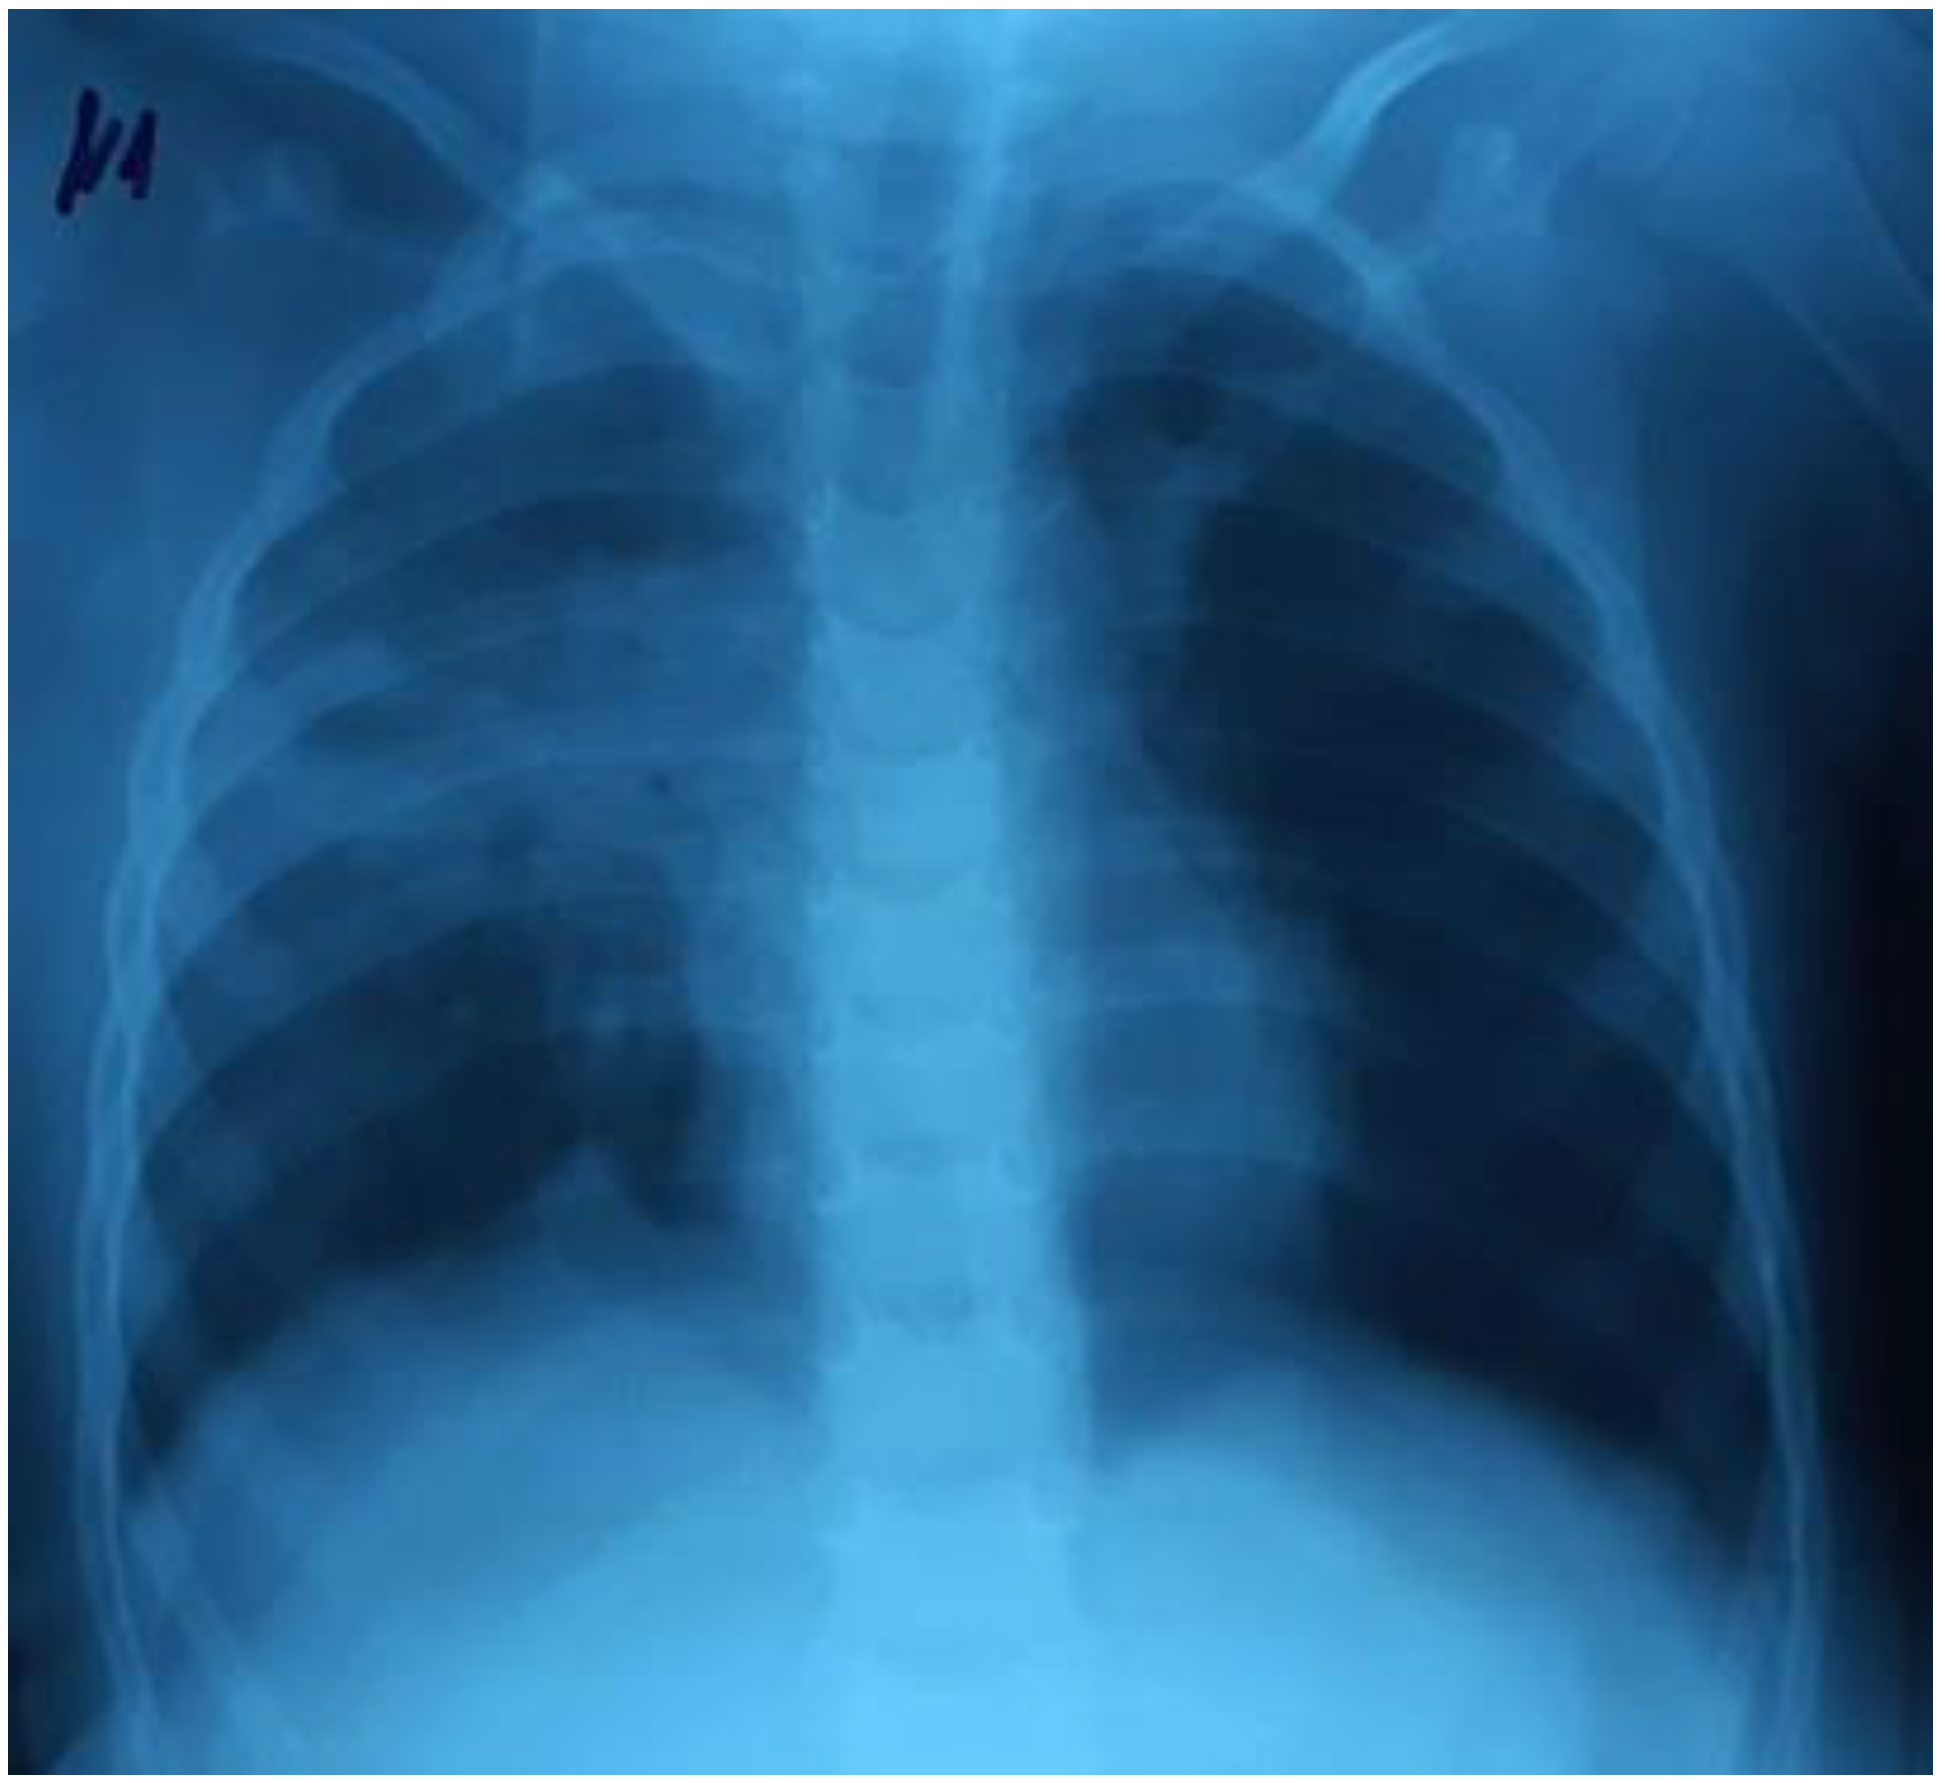

There was a further progression of RF and hypoxemia (PaO2/FiO2 117) on the background of NIV CPAP/PSV in the child, as well as the deterioration of the neurological status of the patient on the Glasgow scale (the decrease in the GCS score from 14 to 12). The control chest X-rays (performed in 24 hours) revealed a deterioration of the radiological imaging (Figure 2).

Figure 2.

The increase of the intensity of opacities on the right side, the appearance of new bilateral infiltrates.